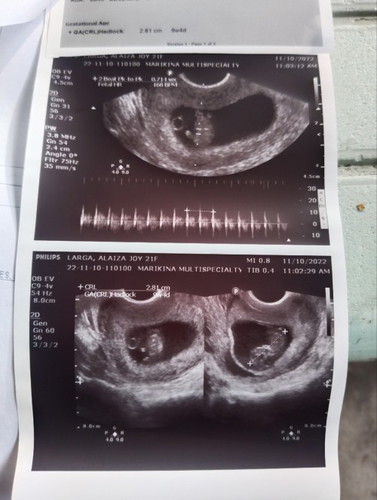

Sinu Po marunung tumingin Ng ultrasound kung NASAn placenta

Ni baby NASA left Po ba or right

Nasa report po usually anterior or posterior high lying or low lying